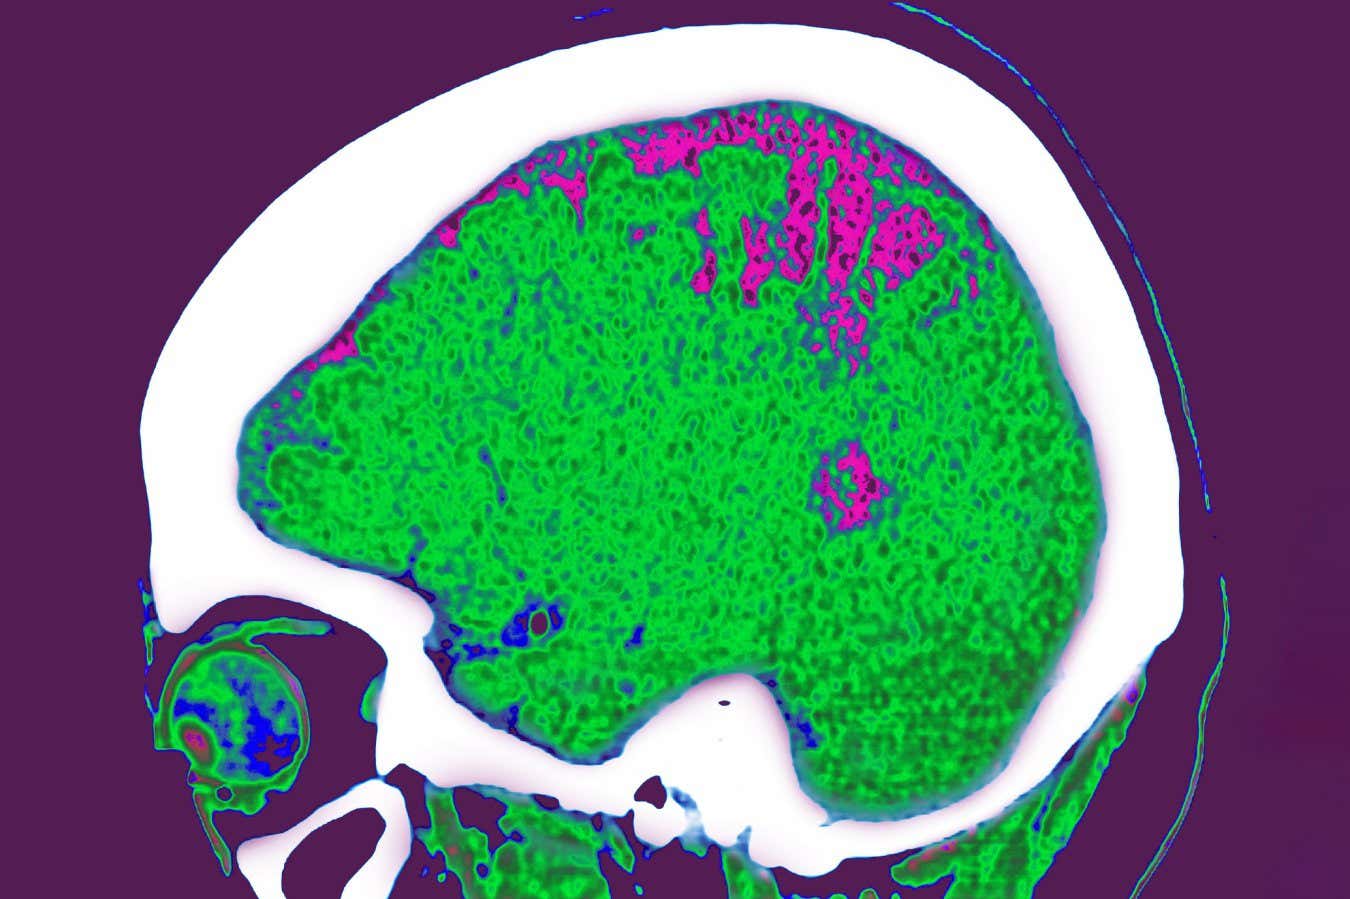

18.000’den fazla insandan gelen veriler, vücutta fazla yağ depolandığı durumlarda beyin yapısı, aktivitesi ve sağlık üzerindeki etkilerini etkilediğini göstermektedir.

Ekip, vücut kompozisyonu taramalarını topladı ve beyin görüntüleme İngiltere BioBank projesine katılan ortalama 62 yaşına sahip 18.000’den fazla yetişkinin sonuçları. Yaş gibi faktörleri oluşturduktan sonra, araştırmacılar bu bölgelerin her birindeki aşırı yağları farklı beyin değişikliklerine bağladılar.

Ancak, visseral yağ olarak bilinen iç organların etrafında, değişen beyin fonksiyonu ile en güçlü ilişkiye sahip olan daha fazla yağa sahipti. Bu, ekibin analiz ettiği, farklı beyin bölgeleri arasındaki sinyalleri ileten doku, doku, doku ile bağlantılı olmayan tek yağ türüydü. Bunun yerine, Alzheimer hastalığının başka bir ayırt edici özelliği olan bozulması ile ilişkiliydi.